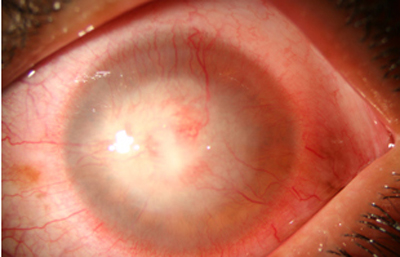

Superficie corneal irregular y grisácea, (Fig. 1, 2) con opácidades granulares en parche y formación de líneas epiteliales elevadas de aspecto granular (Fig. 3), que pueden arborizar dando imágenes de pseudodendritas. Opacidades superficiales satélites. (Figura 4) Inyección ciliar. Ulceración epitelial variante. (Figura 5).

Fig. 1 Síntomas de 15 días evolución